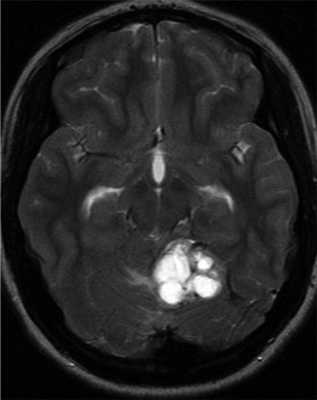

Гемангиобластомы ЦНС могут выявляться в детском возрасте, однако средний возраст диагностирования составляет 29 лет [32, 45, 46]. VHL-ассоциированные гемангиобластомы выявляются в среднем на 15 лет раньше, чем спорадические [47]. В зависимости от размера и местоположения опухоли клинические признаки гемангиобластомы ЦНС включают головную боль, тошноту, головокружение, атаксию, расстройство координации движений, нистагм, расстройства речи. Гемангиобластома спинного мозга может приводить к слабости конечностей и парестезиям. Диагноз устанавливается с помощью МРТ головного мозга и позвоночника. Гемангиобластомы обычно характеризуются медленным ростом и имеют высокий риск кровотечений, часто являются мультифокальными. Понимание патогенеза заболевания важно для выбора оптимального времени скрининга на опухоли и лечение [19]. Исследование тканей ЦНС умерших пациентов помогло пониманию гистогенеза гемангиобластом [49]. Активация фактора, индуцирующего гипоксию 2-альфа (HIF 2-α) происходит в маленьких мезенхимальных опухолях и в мезенхимальном компоненте больших опухолей. Активация HIF 1-α наблюдается в эпителиальном компоненте. Это позволило предполагать, что поражение ЦНС при VHL-синдроме — длительный процесс гемангиобластической пролиферации и дифференцировки [50] (рис. 2). Рисунок 2. Гемангиобластома ЦНС.

Поражения глаз выявляются примерно у 37% пациентов с VHL-синдромом, среди них только у 14% обнаруживается полная делеция VHL [51, 52]. Приблизительно у 8% пациентов снижена острота зрения [53]. Для лечения ангиомы сетчатки используют лазерную или криотерапию [32, 34, 54]. Недавние исследования [ 55, 56] показали, что при внутривенном введении антагониста сосудистого эндотелиального фактора роста (anti-VEGF) в течение 7 мес размер гемангиобластом не уменьшается (рис. 3). Рисунок 3. Ангиоматоз сетчатки.